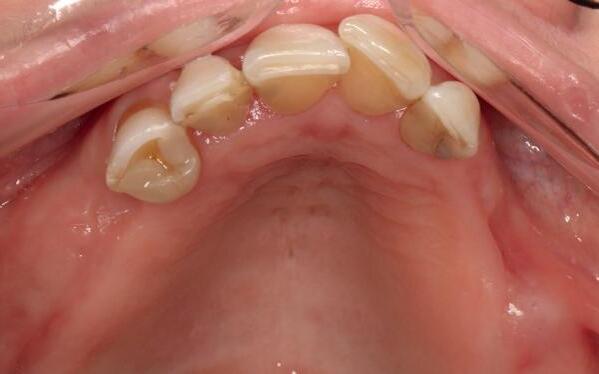

Mevrouw werd naar het Dental Design Center verwezen om een complex probleem aan het bovenfront te beoordelen en indien mogelijk te behandelen. Tien jaar geleden zijn er om esthetische redenen op de 12, 11, 21 en 22 kronen geplaatst. Helaas bleek achteraf een wortelkanaalbehandeling van de 22 noodzakelijk. Na een aantal jaar ontstond er weer een infectie apicaal aan de 22 en werd er een apex uitgevoerd. Helaas had deze behandeling niet het beoogde resultaat. Twee weken voordat ze bij mij op consult kwam, is het element geëxtraheerd en is er een partiële plaat geplaatst als tijdelijke oplossing (foto 1-3).

Na de IPP (esthetisch/functionele) analyse blijkt dat de gezichts- en faciale mediaan niet geheel overeenkomen en dat de gingiva lijnen van het bovenfront niet helemaal parallel lopen met de interpupillaire lijn. Na overleg met mevrouw kiest zij ervoor om dit niet orthodontisch te laten corrigeren. Mevrouw

heeft de nadrukkelijke wens om geen brugconstructie te krijgen. Om die reden is een etsbrug of een conventionele brug geen optie. Daarom bestaat het behandelvoorstel uit vier losse kronen waarvan de 22 implantaat gedragen zal zijn. Een gedetailleerd onderzoek van de regio 22 is noodzakelijk (foto 4-6).

Uit het röntgenonderzoek blijkt dat op de locatie van de 22 veel bot verloren is gegaan en dat er niet direct een implantaat geplaatst kan worden. Om die reden is een botaugmentatie geïndiceerd. Wel zijn distaal van de 21 en mesiaal van de 23 de botpieken aanwezig die de papillen ondersteunen. Naast te weinig bot, is op de locatie 22 in bucco-linguale richting ook te weinig volume gingiva aanwezig. Daarom zal er tevens een soft tissue graft aangebracht worden. Tijdens deze behandeling wordt ook de recessie op de 23 zoveel mogelijk bedekt (foto 7 en 8).